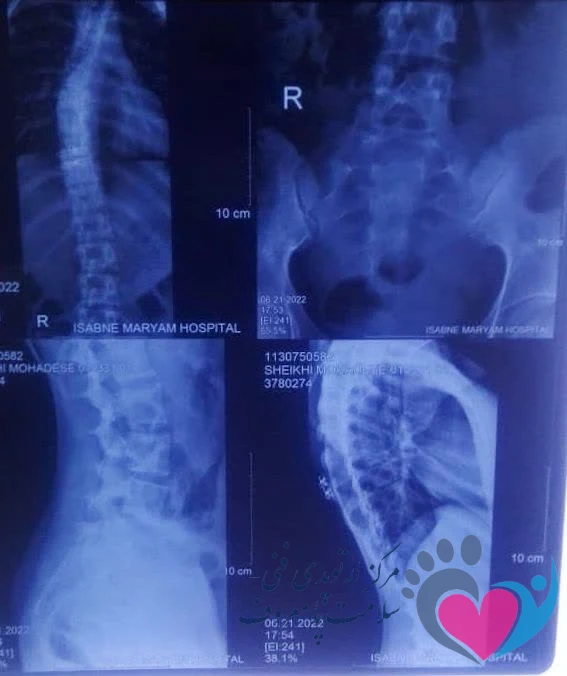

اسکولیوز که به عنوان یک اختلال در ستون فقرات شناخته میشود، با انحراف جانبی و غیر طبیعی همراه است. این انحراف باعث ایجاد خمیدگی در ستون فقرات میشود. نواحی که با احتمال بیشتری درگیر این انحنا میشود شامل بالای ستون فقرات و کمر میباشند.

تشخیص اسکولیوز توسط پزشک متخصص درد و یا ارتوپد و همچنین استفاده از تصاویر تشخیصی مثل پرتونگاری صورت میگیرد. در صورتی که فرد علائم مشابه اسکولیوز را تجربه میکند، مهم است که به پزشک مراجعه کرده و ارزیابی دقیق و درمان مناسب را دریافت کند.